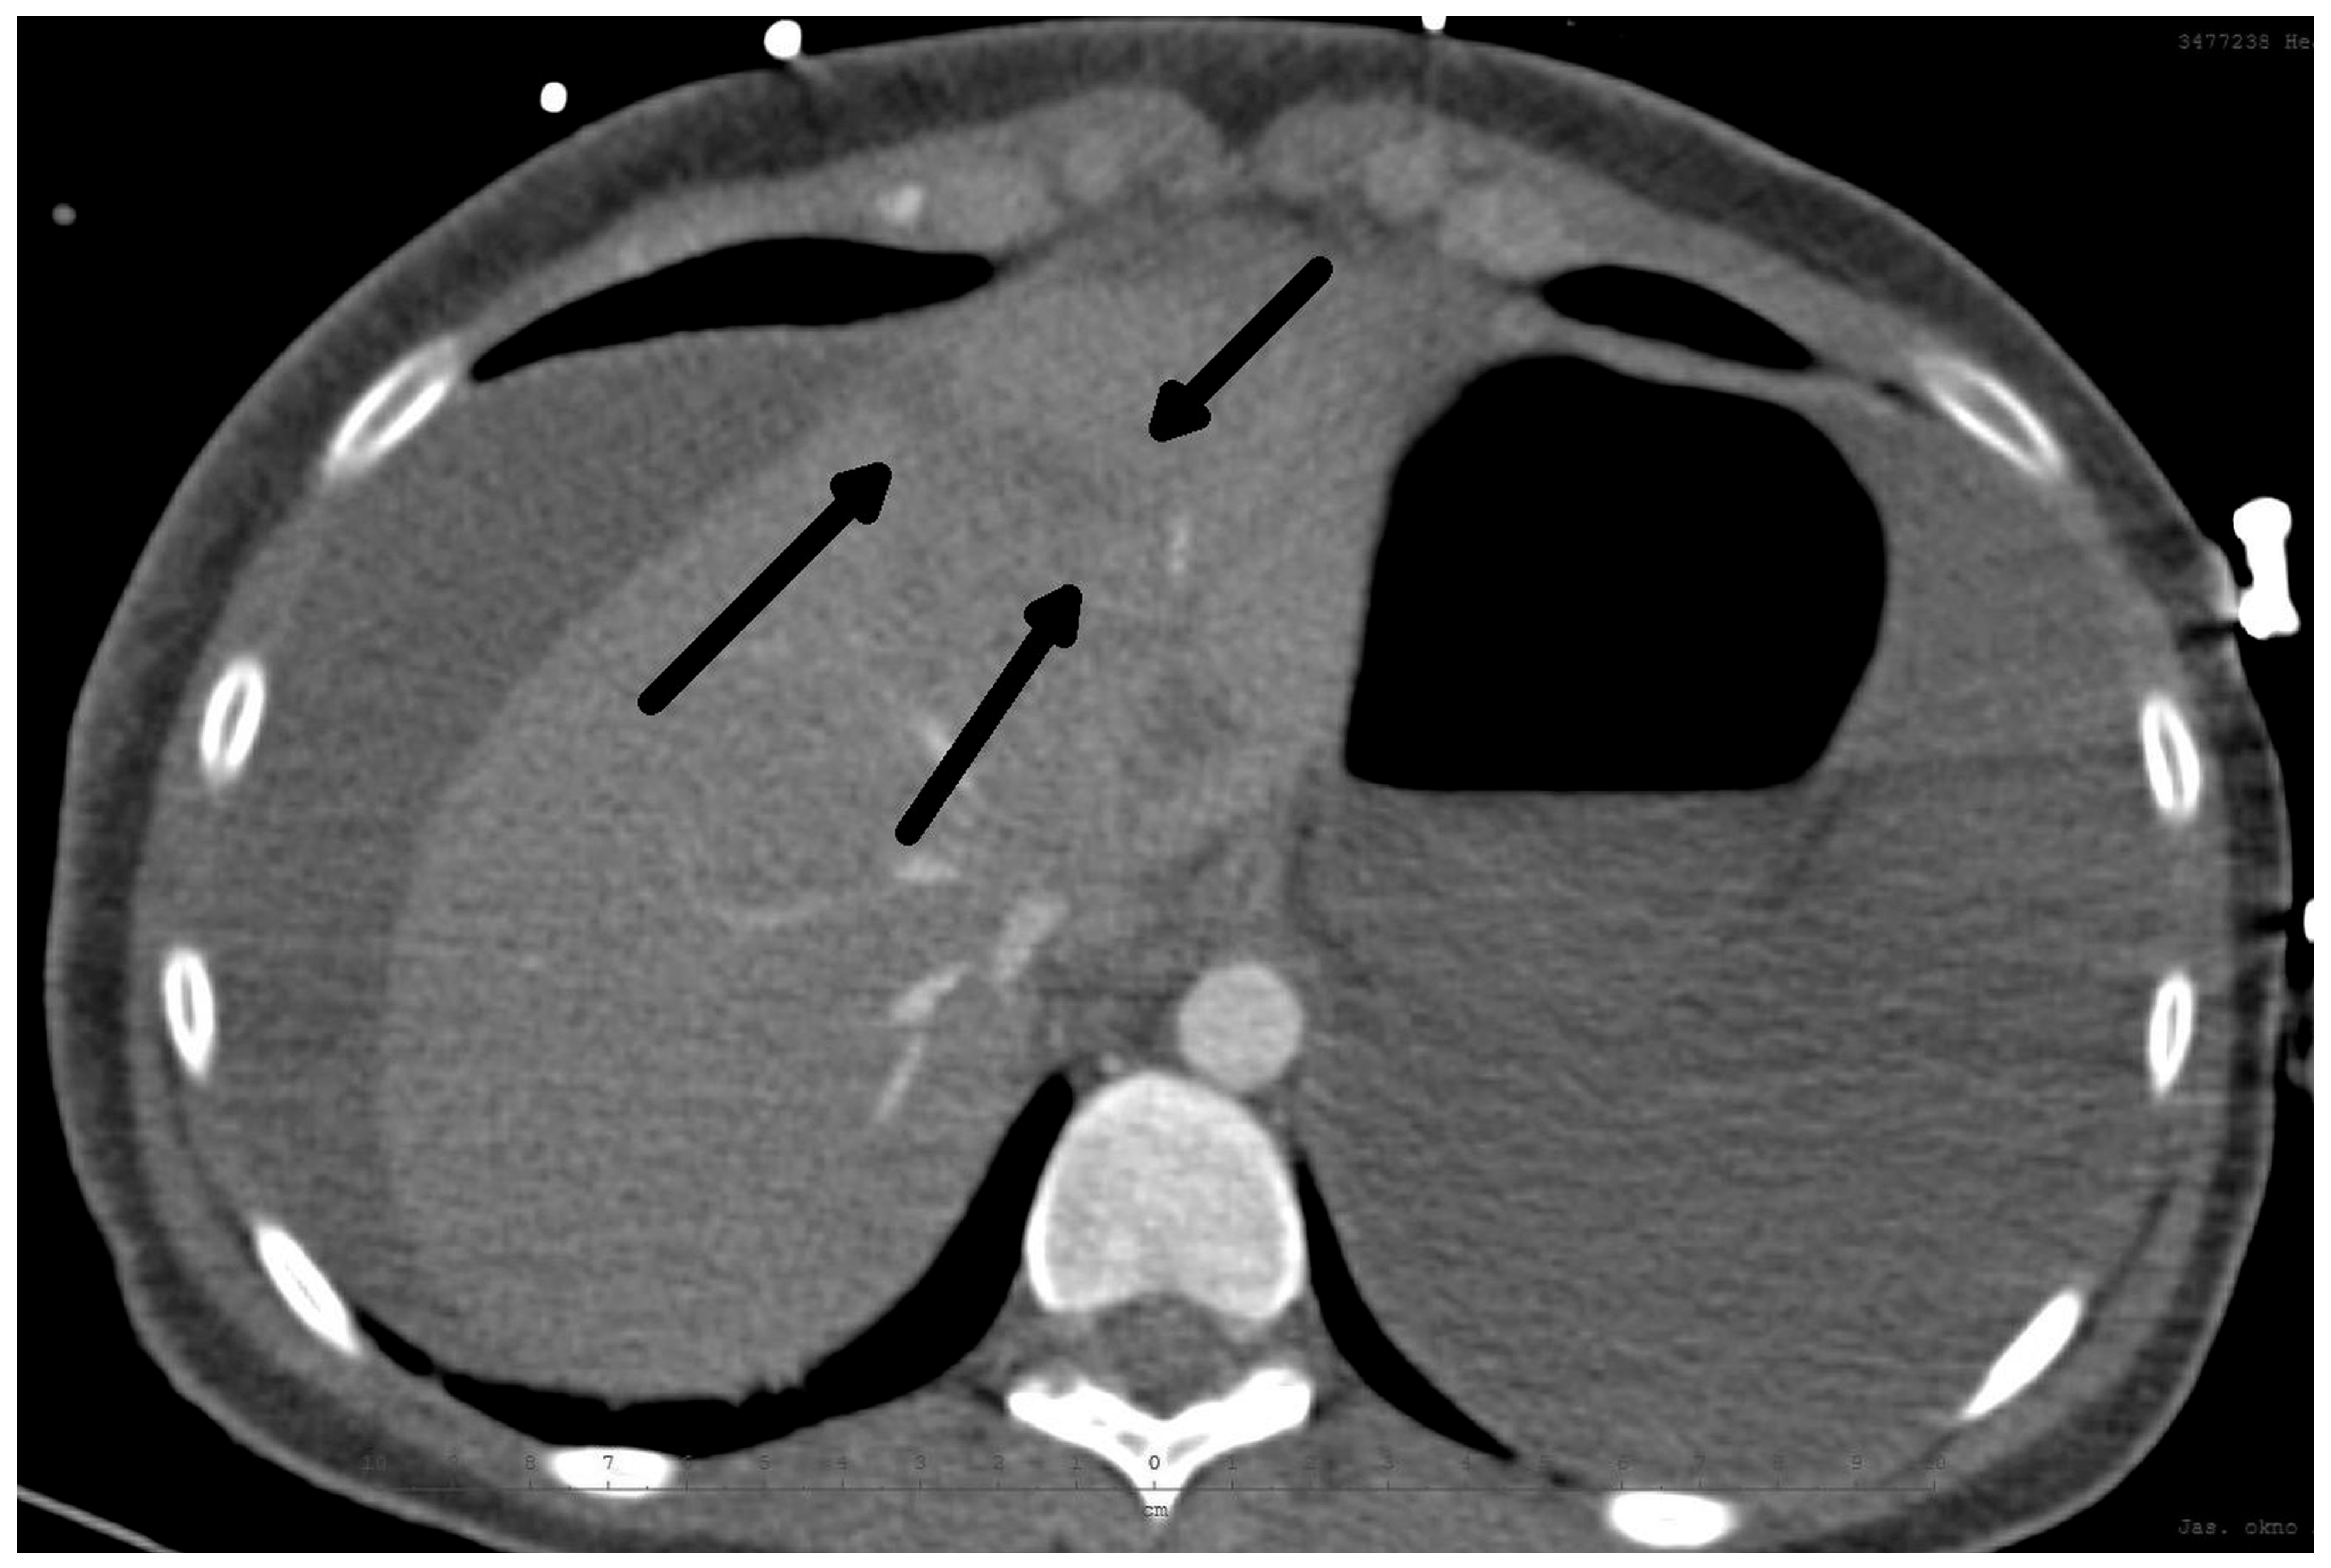

The diagnosis of liver injury was made by clinical and paraclinical examination and confirmed by imaging techniques. (computed tomography (CT) or ultrasound) (Table 2) (Figure 1 and Figure 2).

Figure 1.

CT scan: Rupture of the liver along falciform ligament (arrows) and hemoperitoneum transverse view.